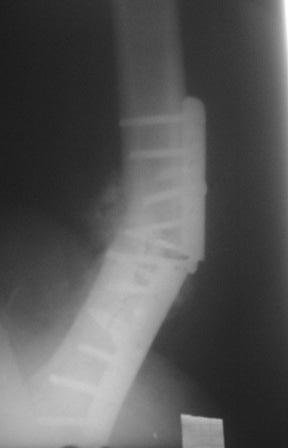

Сегодня больного оперировал.Удаление пластины минидоступом не получилось , т.к. было еше 4 шурупа введенные под разными углами,

они были замурованы к/тканями. Наложено дистракционное устройство по методу А.Н. Челнокова, ротация и угловая деформация устранены, но оказалось в т/б суставе ограничены приведение и внутренная ротация, поэтому пришлось больного укладывать на бок, и с очень большим трудом произведены рассверливание и антеградное введение

гвоздя, у нас ЭОП от комплекта литотрипора США 1993г. его дуга меньше чем обычные ЭОП, для введения запираюших винтов уходит много времени.